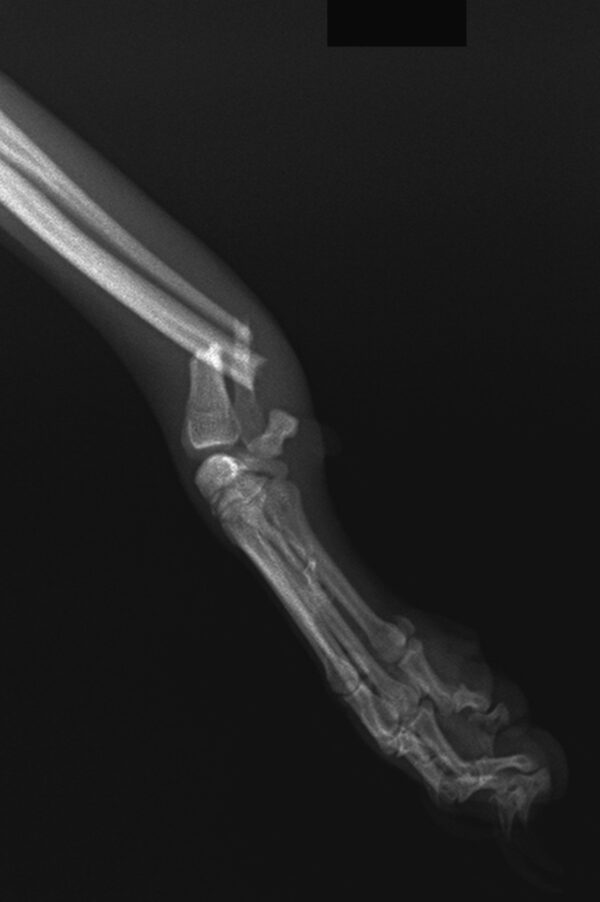

Frattura radio e ulna nel cane toy Currenti Ortopedia Veterinaria

Infortuni e Patologie del Gomito, del Polso e della Mano. Frattura del radio-ulna. La frattura più frequente dell'estremo distale del radio è quella di Colles, tipica dopo una caduta sulla mano atteggiata in iperestensione. Il 60-70% interessa le donne in menopausa ed è tipica dell'osso osteoporotico. Lo stesso meccanismo di caduta nel.. In conclusione, la frattura composta del radio e dell'ulna è una lesione grave che richiede un intervento tempestivo e accurato da parte del medico specialista. Seguire attentamente le indicazioni del trattamento e dedicare il giusto periodo di riabilitazione sono fondamentali per garantire una piena guarigione e il ripristino della.